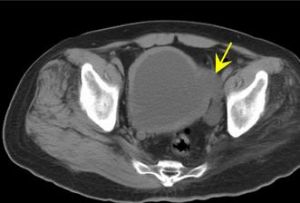

2.檢查①當有會陰部感覺減退,肛門括約肌張力減退或增強時就可確診為神經原性膀胱,但缺乏這些體徵也不能排除神經原性膀胱的可能。②注意有無脊柱裂、脊膜膨出、骶骨發育不良等畸形。③有殘餘尿,但無下尿路機械性梗阻。④電刺激脊髓反射試驗,此法主要試驗膀胱和尿道的脊髓反射弧神經是否完整(即下運動神經元有無病變)以及自大腦皮質至陰部神經核(脊髓中樞)的神經元有無病變(上運動神經元有無病變)。因此,這個試驗即可診斷是滯為神經原性膀胱,又可區分下運動神經元病變(逼尿肌無反射)和上運動神經元病變(逼尿肌反射亢進)。